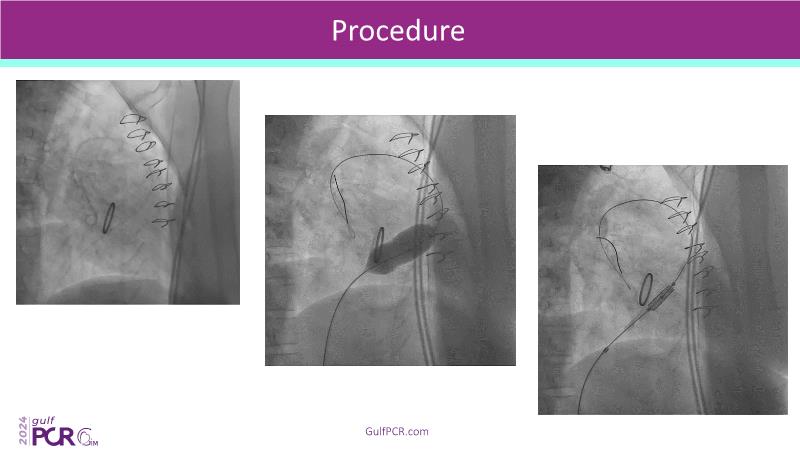

Stay ahead in TAVI innovation by exploring the advanced balloon-expandable Myval THV series. This session highlights the latest clinical data, optimal sizing and implantation techniques, and valuable real-world insights, including long-term follow-up results.

- To learn about the novel balloon expandable Myval THV series and the up-to-date clinical evidence for it

- To understand the best practices for Myval sizing and implantation technique for best outcomes